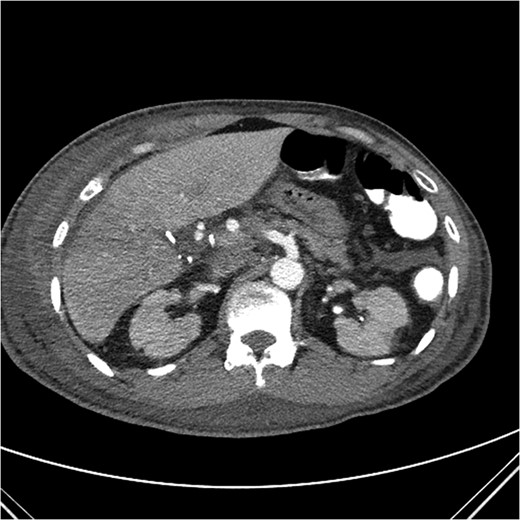

A computed tomography (CT) angiogram of the abdomen was significant for multifocal pneumonia and free peritoneal fluid. Chest CT was negative for pulmonary embolism (Figs 1, 2). Repeat ERCP confirmed a wide-open distal common bile duct at the level of multiple surgical clips with inability to pass a wire distally (Fig. 3). Interventional radiology was consulted to obtain a percutaneous transhepatic cholangiography (PTC) prior to definitive surgical repair.

Coronal CT image with partially visible ERCP stent in the distal common bile duct with surrounding clip artifact.